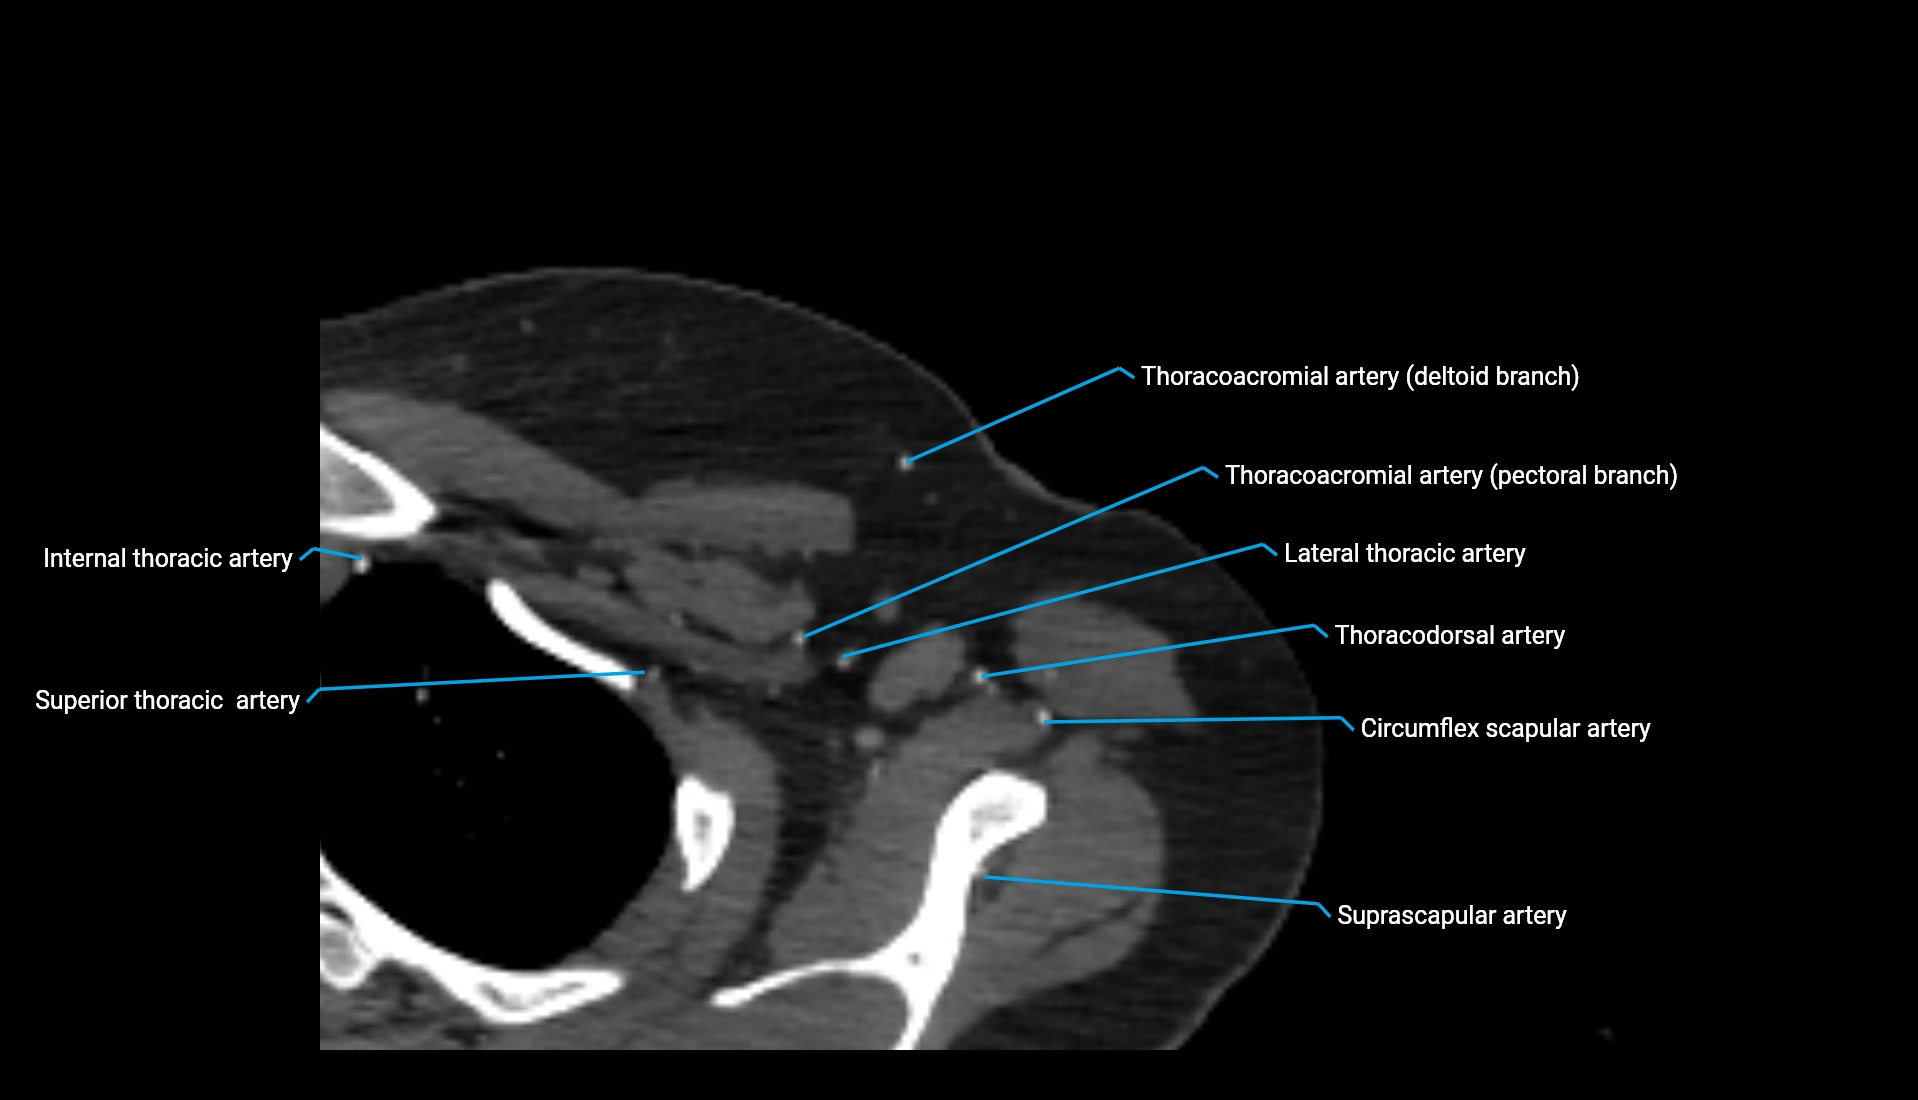

CT Appearance

Non-Contrast CT:

• Cortex: High-density, sharply defined

• Subchondral bone: Dense cancellous matrix

• Articular surface: Smooth concave contour articulating with the capitellum

• Excellent for evaluating bone integrity, alignment, and subtle fractures

Post-Contrast CT:

• Bone: No enhancement

• Joint capsule and synovium: Mild enhancement outlining the joint

• Improves contrast between soft tissues and bony margins

• Useful in detecting subtle joint abnormalities or postoperative changes